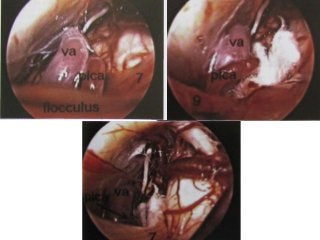

Different positions of the anterior inferior cerebellar artery (AICA) in relation to the

Fig. 74a, b The reference level is the acousticofacial nerve

bundle. The anterior inferior cerebellar artery, lying between

the auditory and facial nerves, is found in 38% of cases.